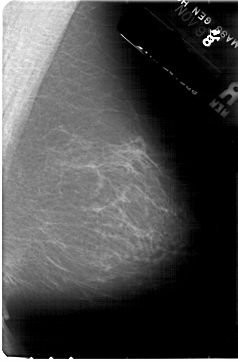

A_1872_1.LEFT_MLO

LEFT_MLO LINES 5491 PIXELS_PER_LINE 3211 BITS_PER_PIXEL 12 RESOLUTION 43.5 OVERLAY

FILE: A_1872_1.LEFT_MLO.OVERLAY

TOTAL_ABNORMALITIES 1

ABNORMALITY 1

LESION_TYPE CALCIFICATION TYPE PLEOMORPHIC DISTRIBUTION CLUSTERED

ASSESSMENT 4

SUBTLETY 1

PATHOLOGY MALIGNANT